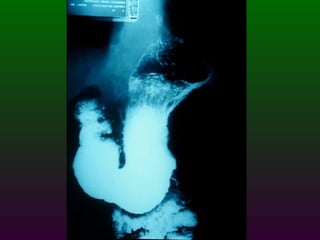

S.E.G.D.  Serie esófago gastro duodenal Definición  Estudio de doble contraste (bario) y aire del tracto digestivo superior. (esófago, estómago, duodeno)

SEGD. VALORACIÓN: Tamaño Longitud  Capacidad de distensión (calibre) Llenado Vaciamiento Patrón: Mucosa

SEGD Puntos normales de estrechamiento del esófago A nivel cartílago cricoides Altura de botón aórtico Donde cruza el bronquio izquierdo El sitio donde pasa a través del diafragma

SEGD PATOLOGÍA  ESOFÁGICA A.- Estrechamientos y dilataciones secundarias Acalasia Estenosis Esclerodermia Enf. de Chagas Neoplasia Lesiones por quemadura (cáusticos y dietéticos etc.)